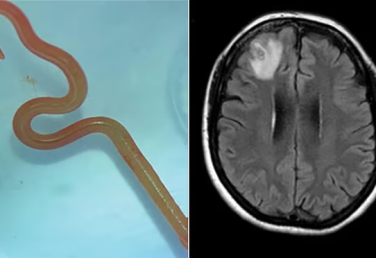

Australia: Phát hiện giun tròn sống ký sinh trong não người

Các bác sĩ Australia vừa tìm thấy một con giun dài 8 cm, sống ký sinh bên trong não của nữ bệnh nhân 64 tuổi, khi lấy ra vẫn còn sống.